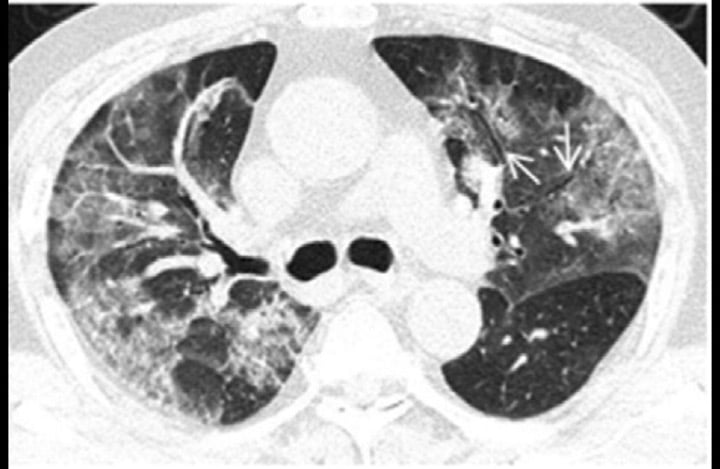

طبق یک مطالعه موردی، یک زن ۳۳ ساله با تب و سرفه پنج روزه، دمای بدن ۳۸.۸ درجه، مشکل تنفسی و تعداد پایین گلبولهای سفید خون، نشانهای از عفونت، به بیمارستانی در لانژو چین مراجعه کرد.در سی تی اسکن اولیه، محققان بیمارستان دانشگاه لانژو «کدورت شیشه مات» را در گوشه پایین ریههای وی شناسایی کردند.به این بیمار اینترفرون، پروتئینی برای درمان عفونتهای ویروسی، تجویز شد اما سه روز بعد (و بعد از درمان او) علائم بارزتر شدند. همین اتفاق در بیماران SARS نیز رخ داده است. «اگر از این شیوع اطلاع نداشتیم با مشاهده اسکن تشخیص پنومونی میدادیم، زیرا این شایع ترین چیزی است که میبینیم.»«ذات الریه معمولاً به سرعت پیشرفت نمیکند»، بنابراین این مورد منتفی است.اسکن ریه کرونایی یک خانم ۲۷ ساله که در ووهان کار میکرد، یک «هاله شیشه مات» را نشان داد؛ لکههای سفیدی که ندول کوچکی را احاطه کردهاند.

«هاله شیشه مات» میتواند یکی از ویژگیهای متمایز عفونتهای ویروسی و پنومونی باشد.«هاله شیشه مات» میتواند یکی از ویژگیهای متمایز عفونتهای ویروسی و پنومونی باشد.محققان دانشگاه پزشکی آنهویی در هفی، چین این زن را پس از بستری شدن در اثر تب و سرفه مورد بررسی قرار دادند. بیمار اختلال تنفسی نیز داشت. محققان گفتند: «هاله شیشه مات» میتواند یکی از ویژگیهای متمایز عفونتهای ویروسی و پنومونی باشد.پس از چهار روز بستری در بیمارستان، ندول ریه راست بیمار رشد کرده بود.برخی از بیماران «الگوی انتشار پیشرونده» را نشان میدهند که به خطوط کم درون کدورت شیشه مات اشاره دارد.